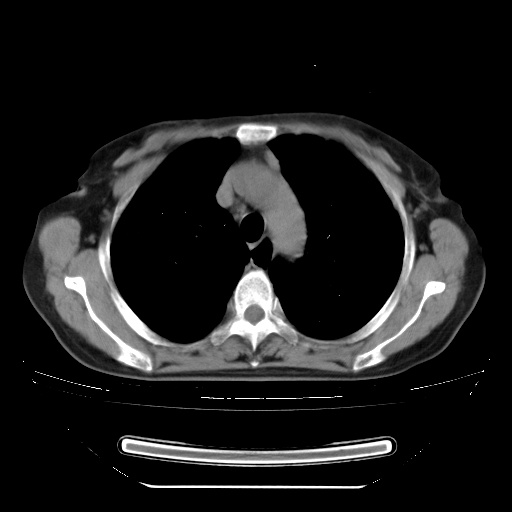

患者女性,72岁,慢性咳嗽3月余,曾抗炎治疗无效果,最近抗结核治疗约半月余,症状缓解。

ct示两肺粟粒状病灶,以两肺上叶尖后段及下叶背段分布为主;首先考虑结核。请战友们分析。